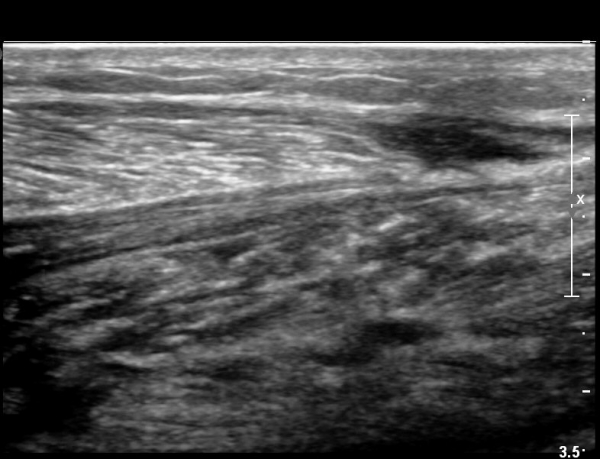

¾ÆÅ³·¹½º°Ç Àú¿¡ÄÚºÎÁ¾ÀÌ °¨¼ÒµÇ°í  ÆÄ¿­ºÎÀ§ Àú¿¡ÄÚ°¡ È£ÀüµÇ¾î

°ÇÀÇ ¼¶À¯¼º¾ç»ó(fibrillar pattern)ÀÌ È¸º¹µÇ°í ±¹¼ÒÀû ¿¬°á¼º ¼Ò½ÇÀÌ »ç¶óÁü(»çÁø 9, 10, 11, 12).

Ä¡  ·á : ¾à 5°³¿ù °£ PRP ÁÖ»ç 2ȸ , Ãæ°ÝÆÄÄ¡·á 6ȸ ½ÃÇà.

°æ  °ú : 5°³¿ù ÈÄ º¸ÇàÀº Á¤»ó ¾ç»óÀ¸·Î ȸº¹µÇ°í, ¹ß³¡À¸·Î ¼­±â°¡ °¡´ÉÇϳª Á¤»çÃø¿¡ ºñÇØ ¾àÈ­¸¦ º¸ÀÓ.